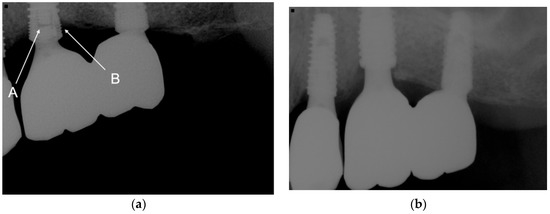

| Implant types | IT | 1379 |

| IU | 401 | |